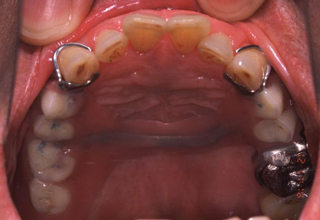

患者の口腔内 患者の口腔内

図3a 初診時

図3は、発音しづらさを訴えて来院した患者の初診時と新義歯装着時の口腔内写真である。

それでは初診時の義歯はどこが問題があるのだろうか?

それでは前出の症例についてであるが、図3aに示すように口蓋前方部に床が伸びており、またその床の厚みが大きい。この部分の義歯の厚みが大きくなると“サ”行、“タ”行が発音しづらくあめ玉をしゃぶったときのような発音になってしまう。そのため図に示す部位を薄くするか義歯床を短くすることが重要である。